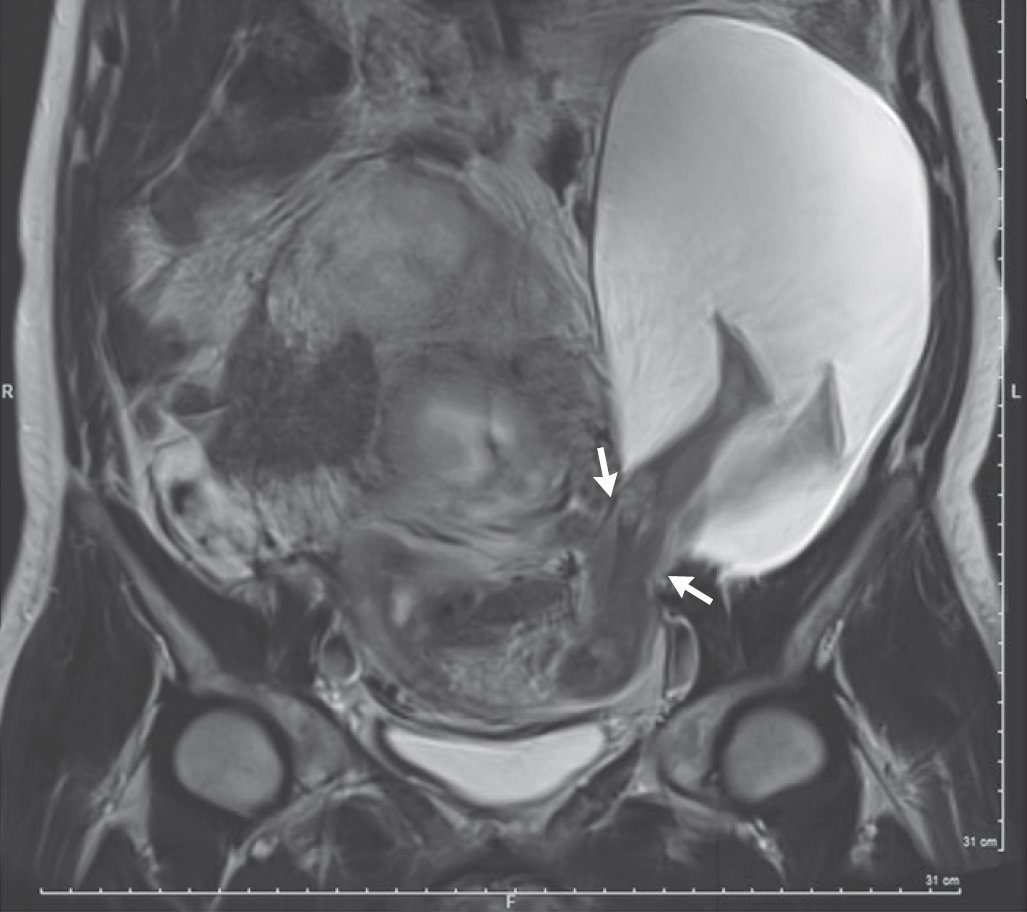

Images in Clinical Medicine: Uterine Rupture with Protruded Legs http://nej.md/2hRv5oc pic.twitter.com/GxEXlaNCwm